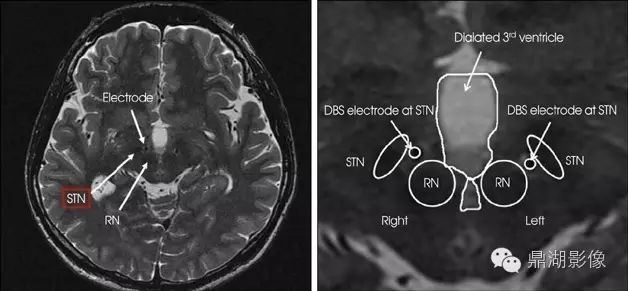

丘脑底核

即Luys核,为一梭状结构,位于间脑的基部和中脑脚的移行处,中脑大脑脚的背面,正好是内囊转人大脑脚的转折处。目前认为它可能为黑质的延续。在人类中此核较大。

红核

左右各一,位于中脑中线的两侧,黑质之背内侧。横断面呈微红色的圆形核团,接受小脑的神经纤维,并发出红核脊髓束。红核及其联系神经受损时,可引起小脑性动作性震颤或小脑性共济失调。